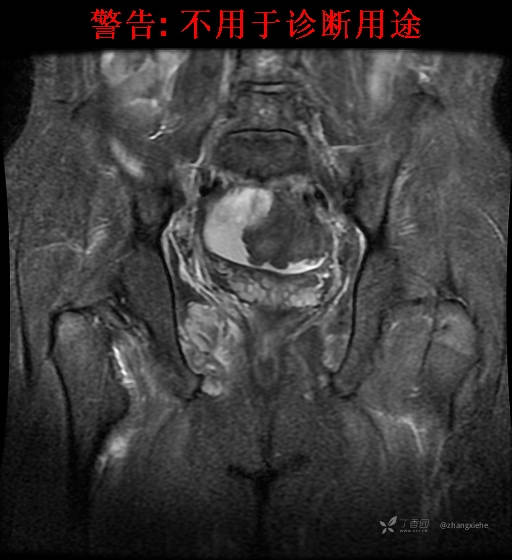

现病史:患者2022-02-07在市中医院体检发现右肺占位,胸部CT示:右肺下叶基底段见一不规则软组织密度影,增强扫描呈轻中度强化,可见血管贴边征。当时无任何不适。2022-02-24于省肿瘤医院行纤支镜检查阴性,痰检未找到癌细胞。经皮肺穿刺细胞学检查找到高度癌疑细胞,病理示:右下肺穿刺考虑神经内分泌癌。免疫组化结果:CgA(-)、CD56(-)、Syn(+)、CK广谱(-)、p40(-)、P63(少量+)、TTF-1(-)、Ki-67(+,40%)、NapsinA(-)、Calcitonin(-)、TG(-)。ECT示:全身骨扫描未见明确骨转移征象。患者出现贫血且逐渐加重、低蛋白血症,予人促红素注射液、精蛋白重组人胰岛素混合注射液、人血白蛋白对症处理,效果不明显,病情加重,右髋出现疼痛,不能行走。2022-03-04转院南大二附院进一步治疗,2022-03-20行右侧髂骨穿刺活检术,术后病理结果示:考虑软组织透明细胞肉瘤。免疫组化示:瘤细胞Vim(+)、NSE(+)、S-100(+)、SOX10弱(+)、Melan-A(+)、TFE-3部分弱(+)、CK(-)、MyoD1(-)、Desmin(-)、HMB45(-)、CD34(-)、CD68(-)、CR(-)、Ki-67约15%(+)。特殊染色示:网状纤维染色(-)、PAS(±)。

2022-03-05血常规示:血红蛋白:64g/L,生化示:白蛋白20g/L。骨髓涂片细胞学检查示:骨髓增生明显活跃,粒红比减低。粒、红、巨三系增生明显活跃。粒系伴成熟障碍。髓片浆细胞较易见,占7%。粒系增生明显活跃,核明显左移,可见巨幼样变及核浆发育不平衡。PET-CT示:1.右肺下叶软组织肿块、右侧耻骨下支及耻骨联合处骨质破坏伴软组织肿块形成,FDG代谢均异常增改,考虑恶性病变,建议病理检查;右侧髂血管旁、双侧腹股沟淋巴结反应性增生,建议随访。2.多浆膜腔(双侧胸腔、心包腔、盆腔)少量积液。3.全身骨骼FDG代谢弥漫增高,考虑骨髓反应性增生。4.大小肠条片状FDG代谢增高,考虑生理性摄取。5.右侧上颌窦面膜下囊肿,脑部FDG代谢未见明显异常。6.C7-T1层面后纵韧带钙化。患者乏力加重,卧床不起,不能承重,大小便不顺畅,转院至我院。门诊拟“1.右肺占位并右侧骨盆转移2.低蛋白血症3.中度贫血 4,血糖升高(原因待查)”收入住院。患者发病以来,无胸闷、胸痛,无呼吸困难,偶咳嗽,无咳血,饮食、睡眠欠佳,2个月之内体重减轻约10kg。

右骨盆及双下肢未见畸形,皮温正常,无浅静脉怒张,右腹股沟中点可触及一质韧肿物,大小约6cm*4cm*5cm,边界不清,固定、压痛明显,叩击痛阳性。右髋关节外旋、屈曲受限。右髋4字试验阳性,左侧阴性,双下肢直腿抬高试验阴性。感觉、运动正常,末梢血运良好,生理反射存在,病理反射未引出。